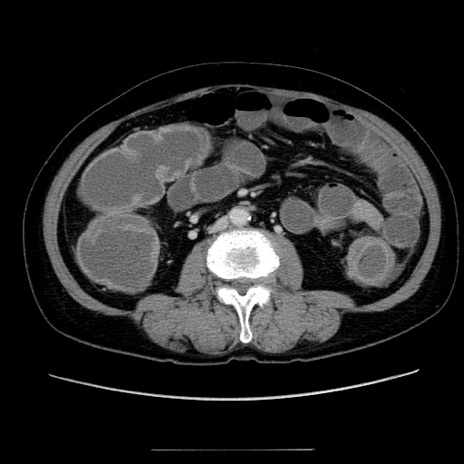

症例5(横断像)

【症例】70歳代女性

【主訴】お腹が張る

【現病歴】1週間くらい前から腹部膨満の自覚あり。昨日夜から増悪したため、本日救急外来受診。

【身体所見】意識清明、BT 36.5℃、BP 165/106mmHg、HR 80bpm、SpO2 98%、腹部:膨満、軟、自発痛・圧痛なし、触診にて不快感あり、腸蠕動音:減弱

【データ】WBC 12600、CRP 1.04